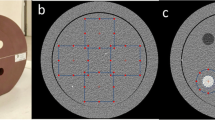

A large-diameter CT-ED table phantom (Advanced Electron Density Phantom; SUN NUCLEAR) was used to measure the CT values and image noise of the various materials. The rods of the advanced electron density phantom mimic water, cortical/inner bone, lung, and liver. They are highly equivalent to the medical standards for human tissue densities and can optimally convert CT values to electron density. Figure 5 shows an overview and analytical view of the phantom. In this study, 10 materials were used, ranging from the lung (electron density: 0.288 c/cm3) to the cortical bone (electron density: 1.774 c/cm3). Moreover, regions of interest (ROI) of mimicked water (electron density: 0.999 c/cm3) were created at the top, bottom, left, and right sides for analysis. The ROI size used in the analysis was approximately 300 mm2, and the ROI was set at the center of each material. CT values and variations (SD) within the ROI were analyzed. The analysis was performed using the viewer provided with the CT device. The CT value is the mean of the CT values within the specified ROI, The SD is the analysis of the variations (1σ) of CT value within the ROI.